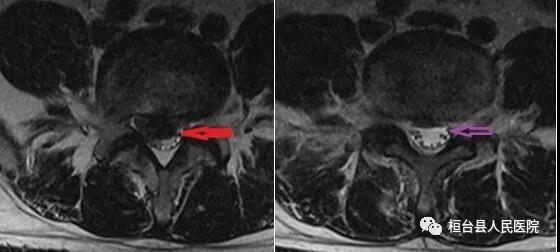

术前巨大髓核下垂,术后脱垂的髓核消失

术前:黑色区域是髓核,术后:黑色区域髓核消失